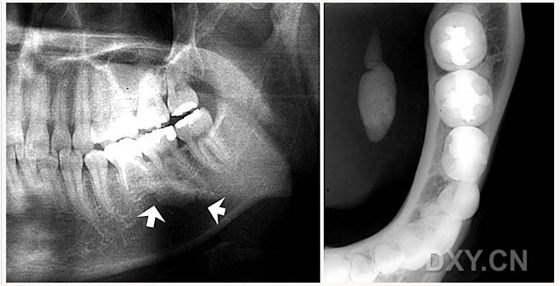

骨肉瘤

涎石病